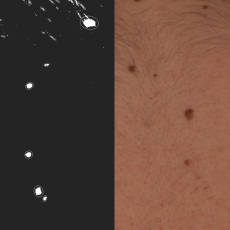

MoleGazer: Applying astronomy ideas to mole identification

Scientists are applying astronomical techniques to identify moles that may develop into the skin cancer melanoma. Astronomers regularly take images of the sky, producing software to map set targets over time. This technology is now being adapted to m…